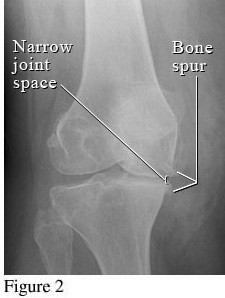

Để phân biệt các giai đoạn của bệnh thoái hóa khớp gối, cần dựa vào phim X- quang theo tiêu chuẩn chẩn đoán thoái hoá khớp của Kellgren và Lawrence như sau:

Hình ảnh của khớp gối trên phim X-quang: Khe khớp hẹp nhẹ, có gai xương nhỏ.

Giai đoạn 2 vẫn được xem là giai đoạn tiến triển nhẹ, xem trên phim X-quang có thể thấy kích thước bề mặt sụn khớp vẫn chưa có sự thay đổi nhiều. Bao hoạt dịch khớp vẫn hoạt động bình thường, cung cấp đủ dịch khớp để nuôi dưỡng sụn và bôi trơn ổ khớp, giúp các đầu xương hoạt động được trơn tru. Mặc dù vậy, bệnh nhân vẫn có thể xuất hiện một số triệu chứng như đau mỏi ở khớp gối sau khi vận động nhiều hoặc khi làm việc quá sức, làm việc sai tư thế; cứng khớp khi trời lạnh hoặc do ít vận động khớp.

Hình ảnh của khớp gối trên phim X-quang: Khe khớp hẹp rõ, nhiều gai xương kích thước vừa, đặc xương dưới sụn, đầu xương có thể bị biến dạng.

Hình ảnh của khớp gối trên phim X-quang: Khe khớp hẹp nhiều, gai xương có kích thước lớn, đặc xương dưới sụn, đầu xương biến dạng rõ.